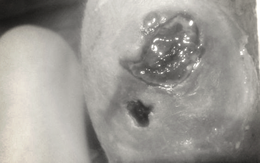

Vi khuẩn Helicobacter pylori (HP) là một trong những nguyên nhân hàng đầu dẫn đến các bệnh lý dạ dày. Việt Nam nằm trong nhóm những nước có tỉ lệ nhiễm vi khuẩn HP cao.